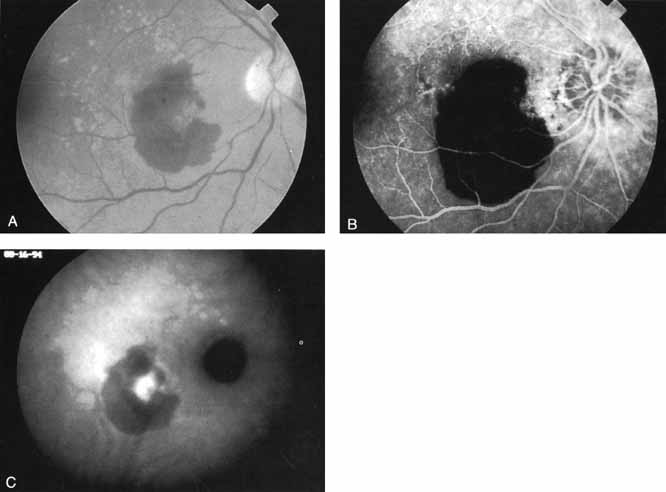

An important report by Chang and co-workers27 lends support to the rationale for interpreting the hyperfluorescence seen on ICG angiography as CNV. In this clinicopathologic study, a patient was identified who had experienced subretinal hemorrhage with early signs of occult CNV on fluorescein angiography (Fig. 4A). Fluorescein angiography demonstrated blocked fluorescence (Fig. 4B). The ICG study, however, demonstrated late staining in a well-circumscribed fashion, which the authors interpreted as a “plaque” of occult CNV (Fig. 4C). When the patient died, this area was evaluated and studied histopathologically and compared with the picture seen on ICG angiography. The area of hyperfluorescence on the ICG study corresponded precisely to a thin layer of fibrovascular tissue beneath the pigment epithelium and neurosensory retina, confirming that the late-staining tissue imaged with ICG angiography was truly a neovascular membrane (Fig. 4D).

Fig. 4 A. Clinical photograph of a patient with exudative age-related macular degeneration demonstrating subretinal hemorrhage. B. Late-phase fluorescein study demonstrating blocked fluorescence from the subretinal hemorrhage. C. Late-phase indocyanine green (ICG) angiogram demonstrating a well-defined area of hyperfluorescence presumed to represent a localized plaque of choroidal neovascularization. Several months after this angiographic study was performed, the patient died and the eyes were obtained for histopathologic examination. D. Hematoxylin and eosin preparation of a section through the retina and choroid in an area corresponding to the hyperfluorescence noted on the ICG study. There is a focal area of fibrovascular tissue beneath the retina. The histopathologic study confirmed the presence of a neovascular membrane in an area corresponding to the zone of hyperfluorescence noted on the ICG study. (Chang TS, Freund KB, De la Cruz Z, et al: Clinicopathologic correlation of choroidal neovascularization demonstrated by indocyanine green angiography in a patient with retention of good vision for almost four years. Retina 14:114, 1994)